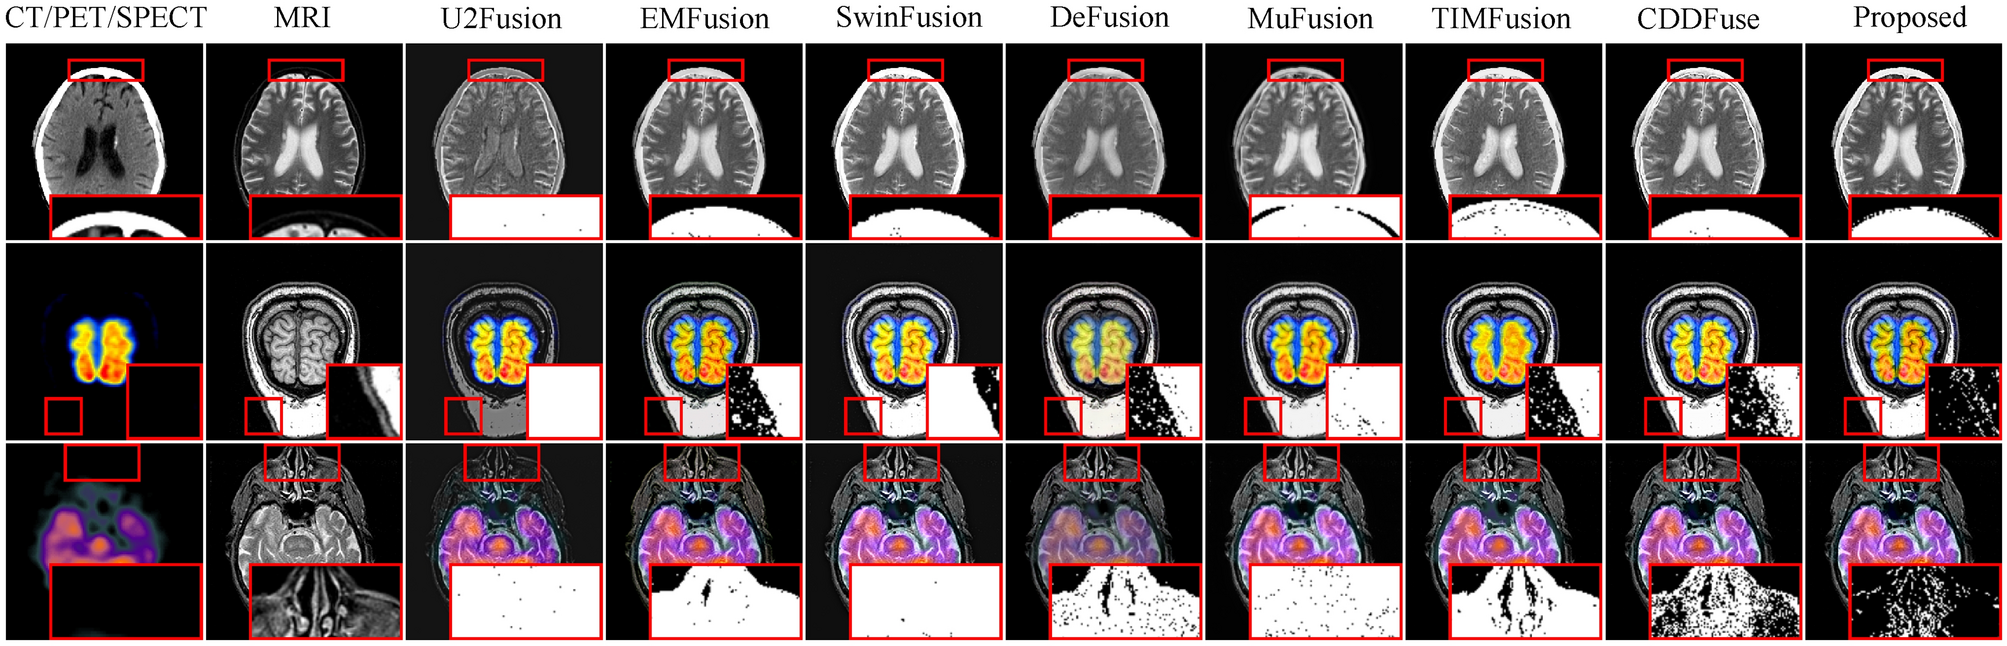

Fig. 9

From: A novel multimodel medical image fusion framework with edge enhancement and cross-scale transformer

This figure illustrates the typical fusion results of each method on the three tasks. The red box in the lower right corner highlights the binary difference image between the fused result and the CT/PET/SPECT image, which facilitates the visualization of the consistency of the fusion results across different methods in both background and salient regions.